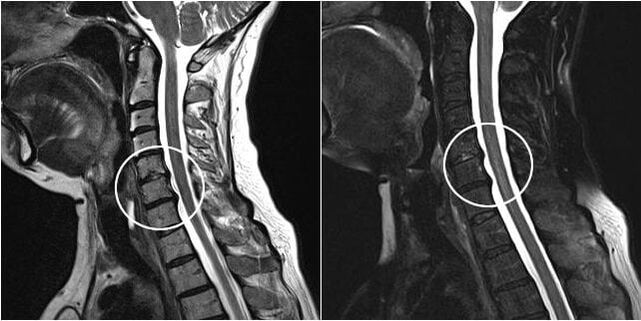

As the intervertebral discs and vertebrae deform, the patient's condition worsens.The course of osteochondrosis is complicated by neurogenic symptoms caused by compression of osteophytes or hernial protrusion of spinal roots and vertebral artery.Headache, dizziness, changes in blood pressure occur, and visual and hearing acuity decreases.

Indications for surgical intervention include the ineffectiveness of conservative treatment, as well as complications of cervical osteochondrosis, for example, discogenic myelopathy, vertebral artery syndrome and radicular syndrome.To decompress the spinal cord, blood vessels and spinal roots, the following operations are performed: